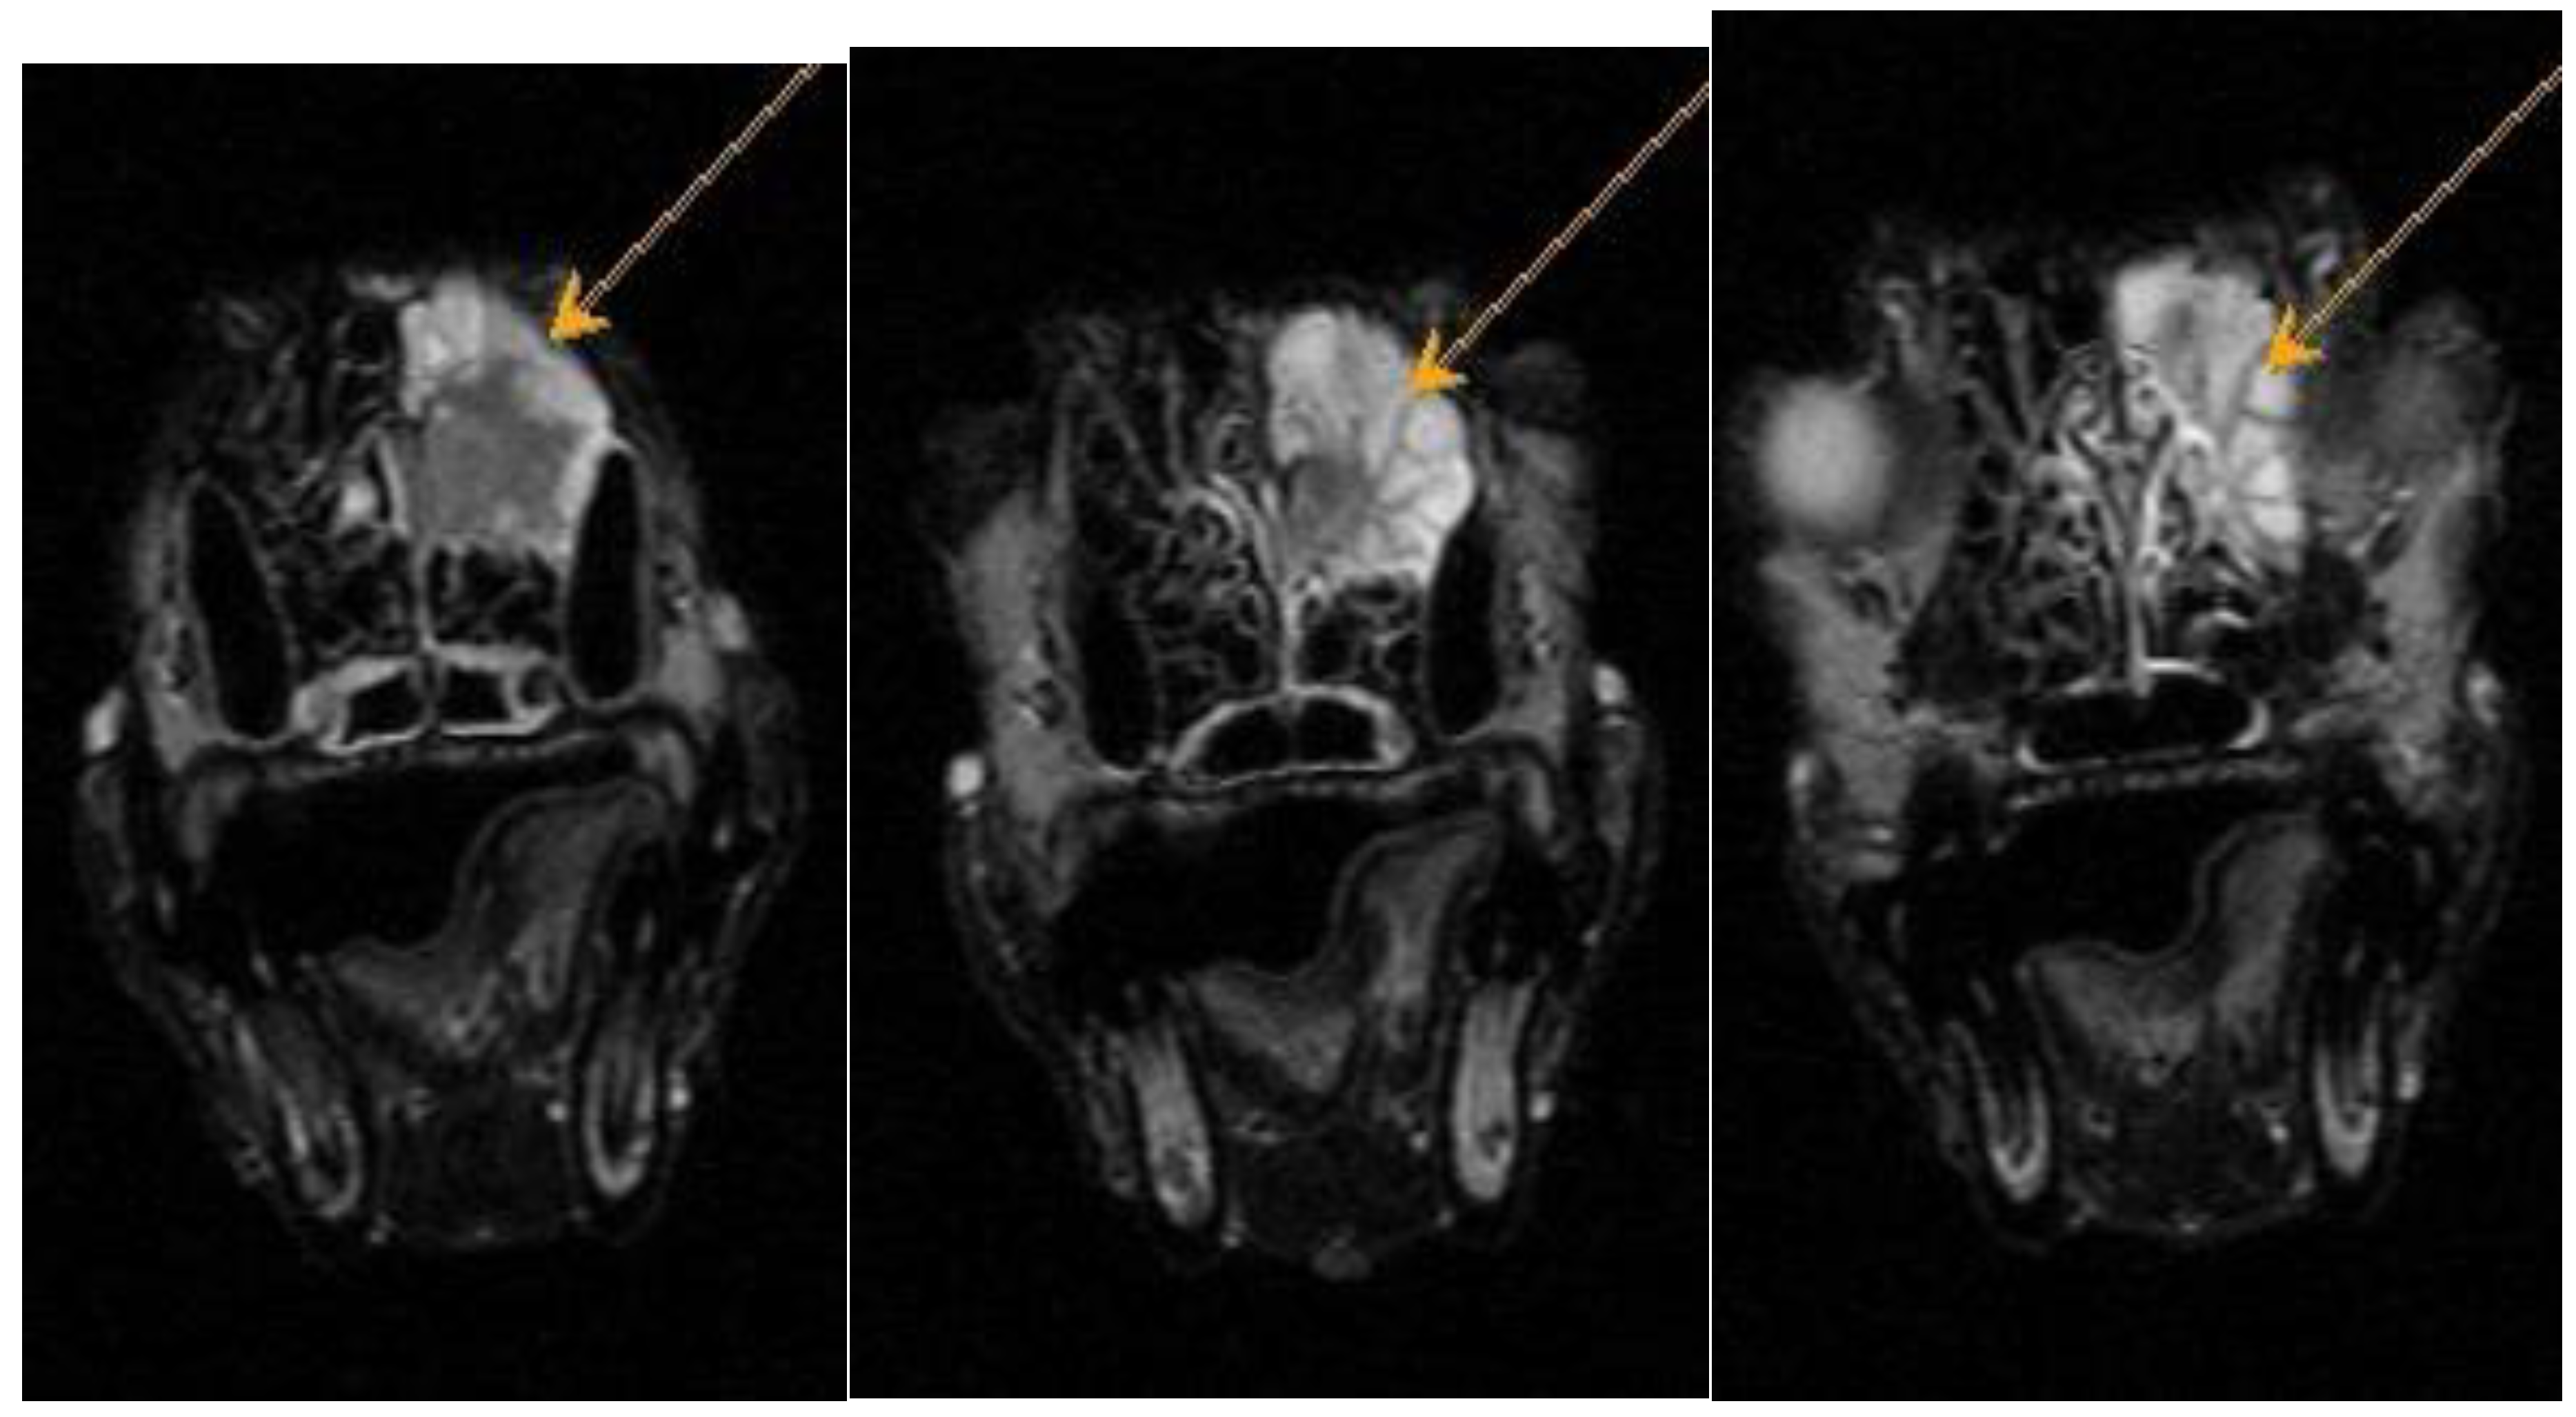

Figure A2. Dachshund dog, 13 years old, 9 kg. T2-VI mode axial plane. Heterogeneous hyperintense signal from the area of the ethmoid bone – neoplasm.

Figure A3. Dachshund dog, 13 years old, 9 kg. FLAIR mode axial plane. Heterogeneous hyperintense signal from the area of the ethmoid bone – neoplasm.